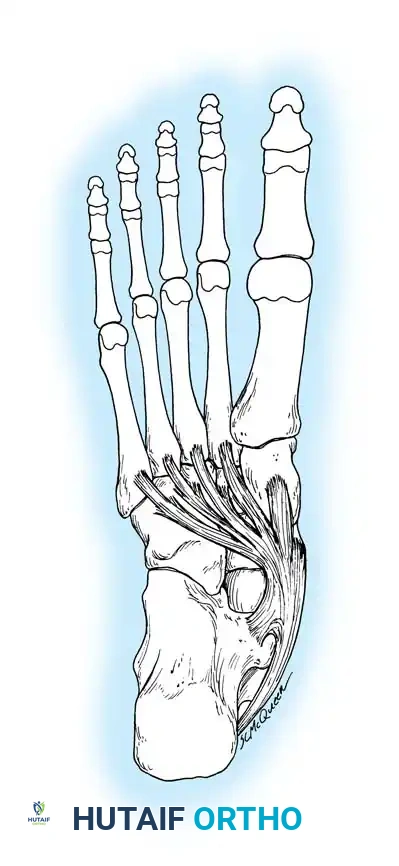

The accessory navicular (os naviculare) is a common accessory ossicle located adjacent to the medial tuberosity of the navicular. When symptomatic, it disrupts the normal insertion and mechanical advantage of the posterior tibial tendon (PTT), contributing to medial arch collapse and rigid pes planus.

The Kidner Procedure involves the excision of the accessory navicular and the transposition/advancement of the PTT to restore its function as a dynamic elevator of the medial longitudinal arch.

Tarsal Coalition: Pathoanatomy and Genetics

Tarsal coalition is frequently, though somewhat inaccurately, grouped strictly under congenital rigid pes planus. While the anatomical defect is present at birth, symptoms rarely manifest until the cartilaginous bar begins to ossify in late childhood or early adolescence.

Embryology and Genetics

The etiology of tarsal coalition is almost irrefutably a failure of primitive mesenchyme to segment by cleavage in the 27- to 72-mm fetus, preventing the formation of the normal peritalar joint complex. This hypothesis was definitively demonstrated by Harris in 1955 through the dissection of fetal hindfeet.

Genetically, tarsal coalition behaves as an autosomal dominant trait with reduced penetrance. Wray and Herndon documented a calcaneonavicular bar across three successive generations of men. Leonard's radiographic survey of 31 index patients and 98 first-degree relatives revealed that 39% of the relatives had tarsal coalitions. Strikingly, not a single one of the affected relatives had any history of foot complaints or peroneal spasticity, suggesting that the true incidence of tarsal coalition in the general population is significantly higher than the traditionally quoted 1%.

Advanced Imaging and Anatomical Reference Gallery

The following images illustrate various presentations, surgical exposures, and advanced imaging modalities (including CT and MRI correlates) utilized in the comprehensive evaluation and treatment of rigid pes planus and tarsal coalitions: